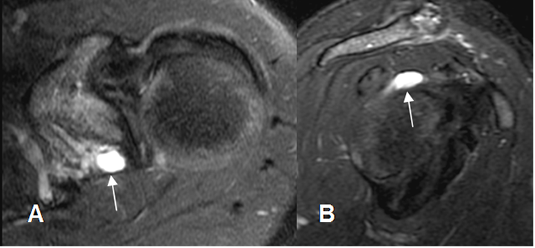

Fig 80. Quiste paralabral.

A: RM axial en STIR y B: RM sagital en STIR. Imagen ovalada y de consistencia líquida, en la parte posterosuperior de la glenoides, que corresponde a quiste paralabral.